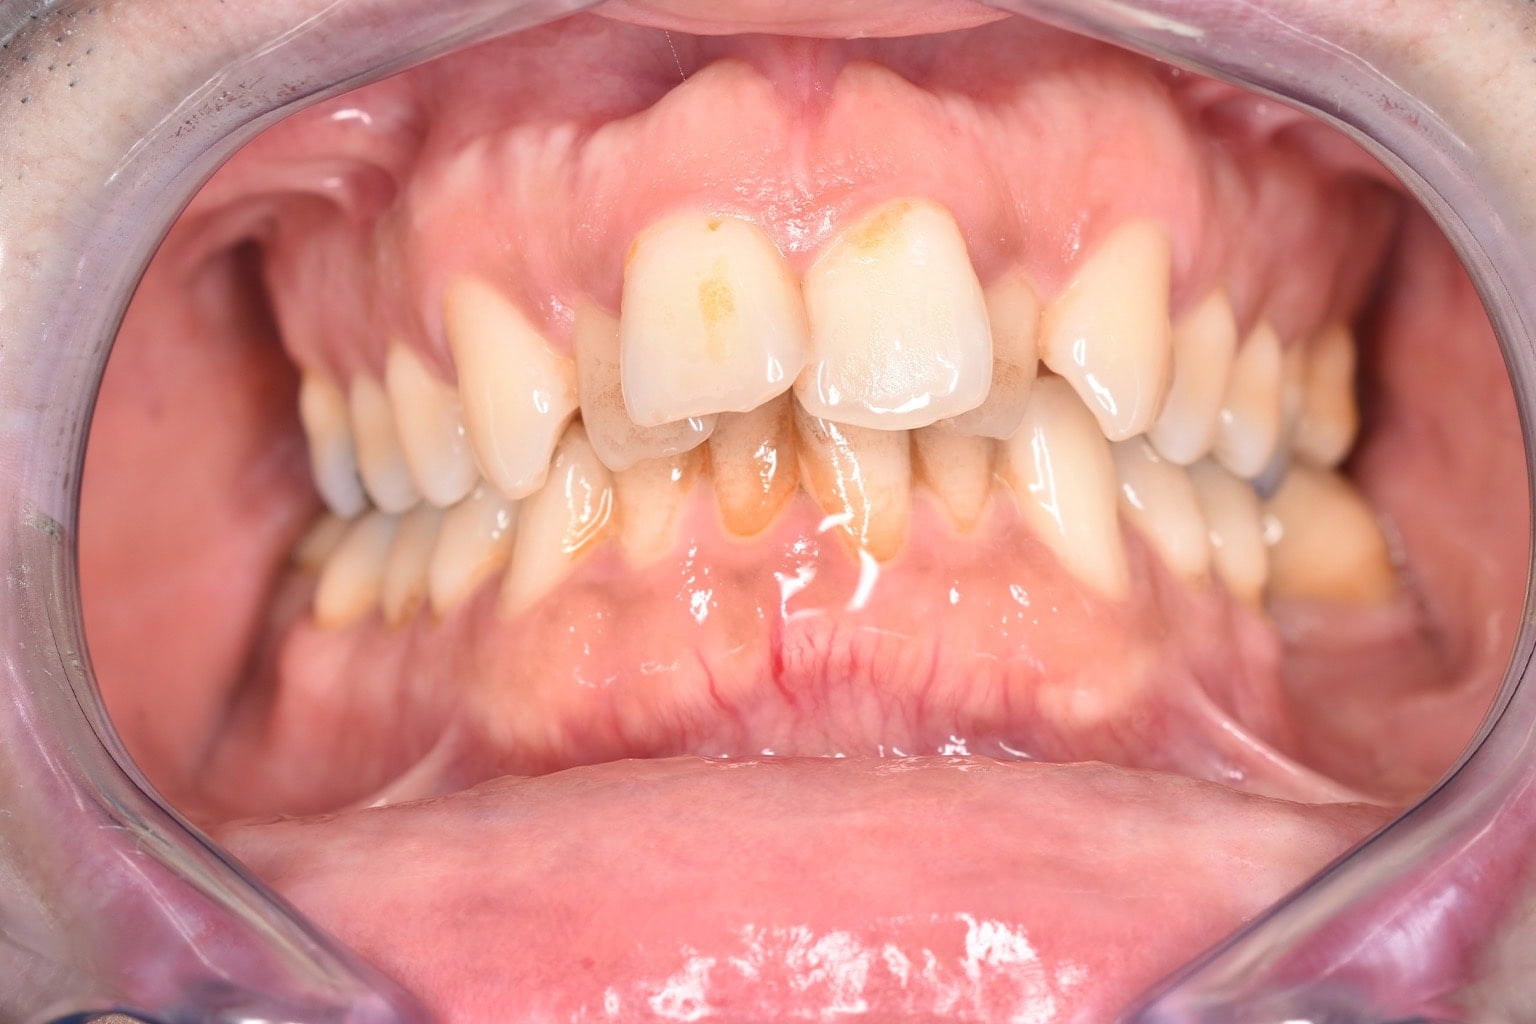

Vorher-Nachher-Ergebnisse

Echte Ergebnisse. Echte Menschen.

Jede Behandlung bei TIEFBLAU Kieferorthopädie ist so individuell wie der Mensch dahinter. In unserer Vorher-Nachher-Galerie zeigen wir Ihnen echte Behandlungsergebnisse aus unserer Praxis in der Kölner Südstadt: Schonend erzielt, präzise geplant und mit dem Anspruch, den wir seit über 40 Jahren an jede Behandlung stellen.

Die Bilder geben Ihnen einen Eindruck davon, was moderne Kieferorthopädie leisten kann, ob bei Kindern, Jugendlichen oder Erwachsenen.

Der sichtbare Unterschied

Dokumentiert. Überzeugend. Nachhaltig.